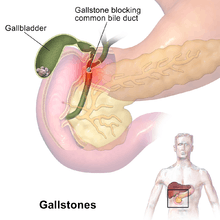

A gallstone is a stone formed within the gallbladder out of bile components.[1] The term cholelithiasis may refer to the presence of stones in the gallbladder or to the diseases caused by gallstones.[2] Most people with gallstones (about 80%) never have symptoms.[1][3] In 1–4% of those with gallstones, a crampy pain in the right upper part of the abdomen, known as biliary colic, occurs each year.[4] Complications of gallstones include inflammation of the gallbladder, inflammation of the pancreas, and liver inflammation.[1][4] Symptoms of these complications may include pain of more than five hours duration, fever, yellowish skin, vomiting, or tea-color urine.[1]

Gallstone disease refers to the condition where gallstones are either in the gallbladder or common bile duct.[2] The presence of stones in the gallbladder is referred to as cholelithiasis, from the Greek chol- (bile) + lith- (stone) + iasis- (process). If gallstones migrate into the ducts of the biliary tract, the condition is referred to as choledocholithiasis, from the Greek chol- (bile) + docho- (duct) + lith- (stone) + iasis- (process). Choledocholithiasis is frequently associated with obstruction of the biliary tree, which in turn can lead to acute ascending cholangitis, from the Greek: chol- (bile) + ang- (vessel) + itis- (inflammation), a serious infection of the bile ducts. Gallstones within the ampulla of Vater can obstruct the exocrine system of the pancreas, which in turn can result in pancreatitis.

Gallstones may be asymptomatic, even for years. These gallstones are called "silent stones" and do not require treatment.[8][9] The size and number of gallstones present does not appear to influence whether or not people are symptomatic or asymptomatic.[10] A characteristic symptom of gallstones is a gallstone attack, in which a person may experience colicky pain in the upper-right side of the abdomen, often accompanied by nausea and vomiting, that steadily increases for approximately 30 minutes to several hours. A person may also experience referred pain between the shoulder blades or below the right shoulder. These symptoms may resemble those of a "kidney stone attack". Often, attacks occur after a particularly fatty meal and almost always happen at night, and after drinking.

In addition to pain, nausea, and vomiting, a person may experience a fever. If the stones block the duct and cause bilirubin to leak into the bloodstream and surrounding tissue, there may also be jaundice and itching. This can also lead to confusion. If this is the case, the liver enzymes are likely to be raised. [11]